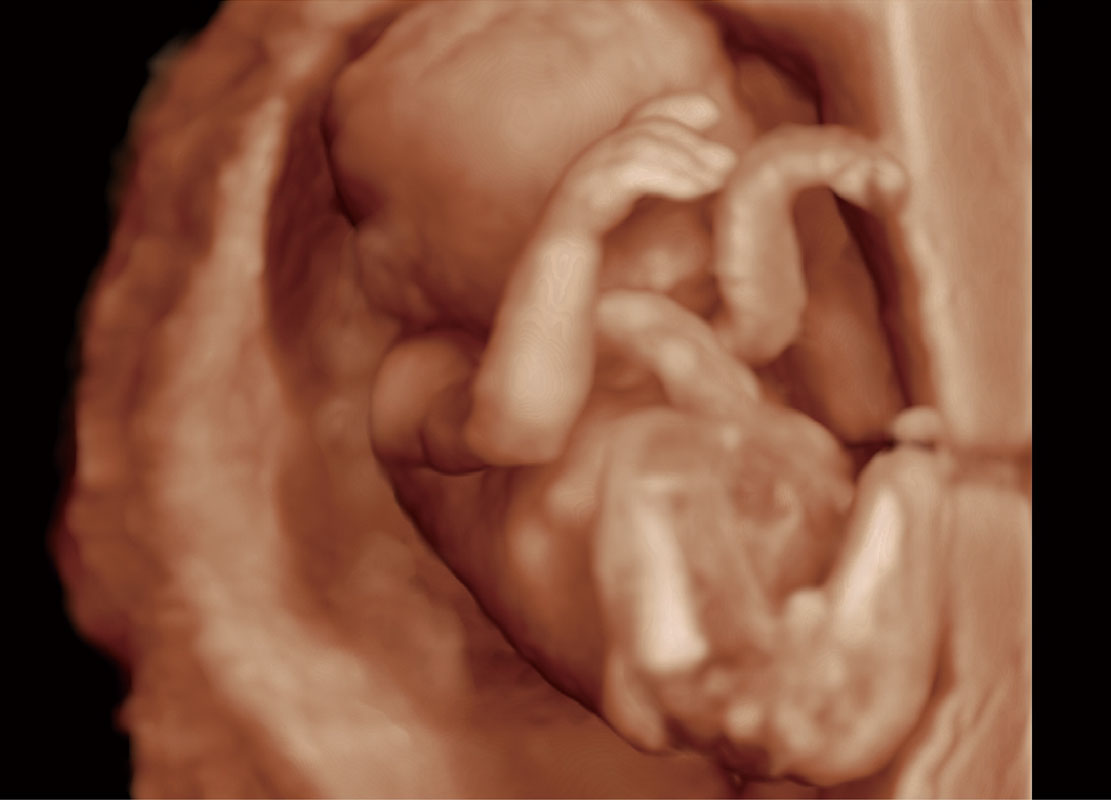

P60在胎兒早孕期超聲篩查中為您帶來(lái)優(yōu)異的圖像質(zhì)量。

高分辨率容積成像-早孕胎兒

胎兒體循環(huán)

光影成像-孕囊